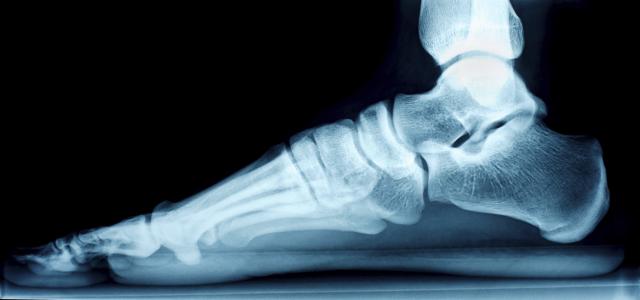

Stopala